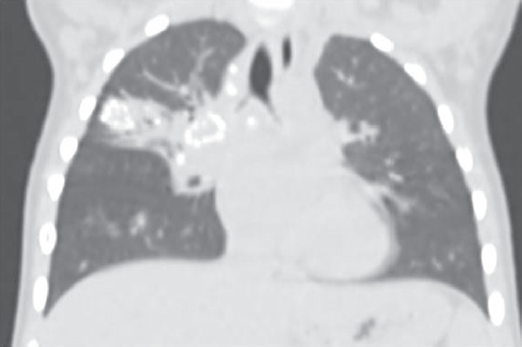

Клинический пример 1. Девочка Л., 3 года, привита БЦЖ в роддоме. По динамике проб инфицирована с гиперергией по ПМ (папула — 18 мм) и выраженной реакцией на ДСТ (папула — 14 мм). При поступлении в стационар отмечались признаки ринофарингита, бронхита. Симптомы интоксикации были выражены умеренно и носили смешанный характер, температура тела нормальная. В клиническом анализе крови лейкоцитоз (14,9 ∙ 109/л) с нейтрофильным сдвигом, ускорение СОЭ (23 мм/ч). На обзорной рентгенограмме — полная норма. Проведена неспецифическая антибактериальная терапия в течение 10 дней — катаральные симптомы купированы. Учитывая эпиданамнез, положительную пробу с ДСТ, выполнена КТ грудной клетки с внутривенным контрастированием — обнаружены единичные кальцинаты в бронхопульмональной группе лимфоузлов справа (рис. 5). Установлен диагноз: «Туберкулез внутригрудных лимфоузлов бронхопульмональной группы справа в фазе неполной кальцинации, МБТ(–)».

Рис. 5. Компьютерная томография грудной клетки девочки Л., три года (туберкулез внутригрудных лимфоузлов)

Fig. 5. Chest computed tomography scan of the 3-years old girl (intrathoracic lymph node tuberculosis)